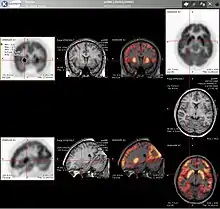

Combination of PET with CT or MRI

PET scans are increasingly read alongside CT or magnetic resonance imaging (MRI) scans, with the combination (called "co-registration") giving both anatomic and metabolic information (i.e., what the structure is, and what it is doing biochemically). Because PET imaging is most useful in combination with anatomical imaging, such as CT, modern PET scanners are now available with integrated high-end multi-detector-row CT scanners (so-called "PET-CT"). Because the two scans can be performed in immediate sequence during the same session, with the patient not changing position between the two types of scans, the two sets of images are more precisely registered, so that areas of abnormality on the PET imaging can be more perfectly correlated with anatomy on the CT images. This is very useful in showing detailed views of moving organs or structures with higher anatomical variation, which is more common outside the brain.

For brain imaging, registration of CT, MRI and PET scans may be accomplished without the need for an integrated PET-CT or PET-MRI scanner by using a device known as the N-localizer.[30][72][73][74]